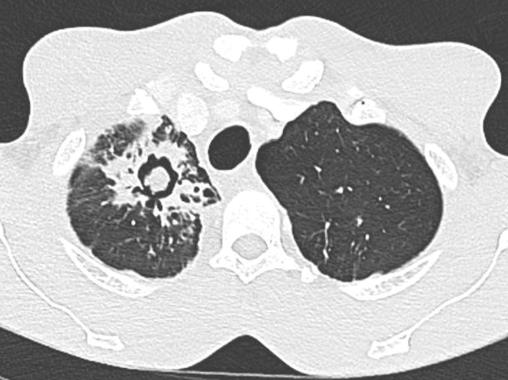

Aspergillose

2. Aspergillose